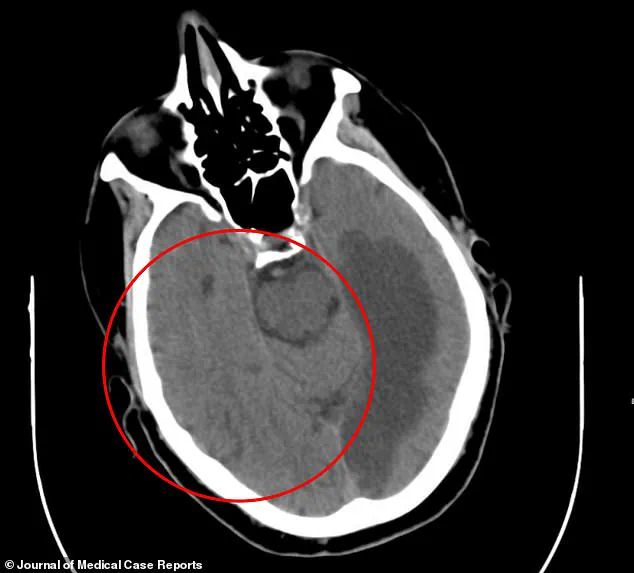

A CT scan of the patient’s brain revealed alarming changes: the distinct gray and white matter typically visible in a healthy brain had blurred together, a sign of oxygen deprivation likely caused by a stroke.

This image, stark and haunting, underscores the fragility of the human brain and the unpredictable consequences of neurological damage.